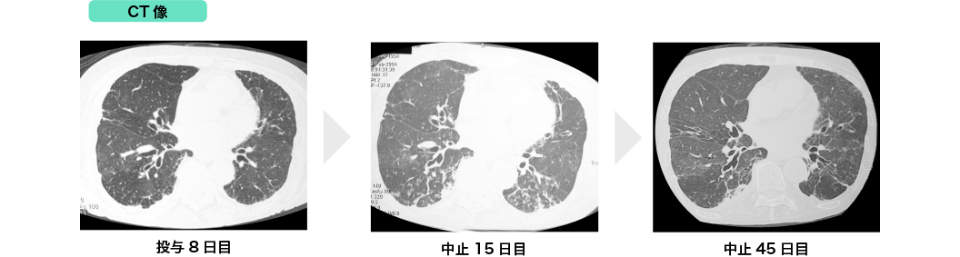

参考症例

(1) 間質性肺炎発現症例